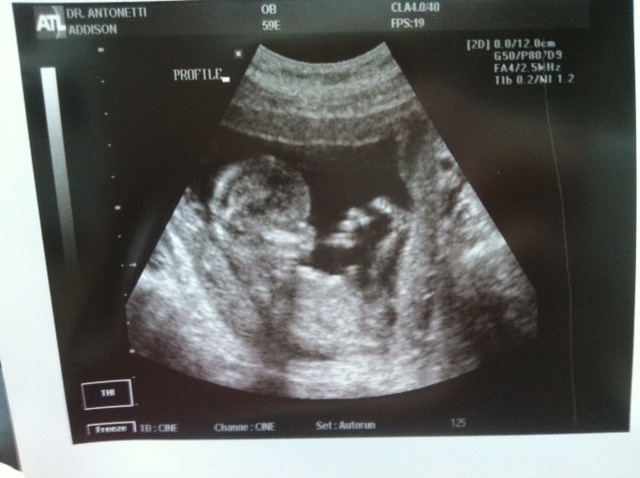

Hi ladies! This ultrasound is 2 weeks ago at my 14 week scan! :baby2: Based on skull theory...do you think it's a boy or girl!? :ttcgirl: I'm happy with either of course although I do have a slight longing for a girl ;-) This is my first pregnancy, and some friends have said girl because of the round lil noggin' lol...and others have said boy!? I can't wait to find out Feb 4th!!! :) Attachment 8313